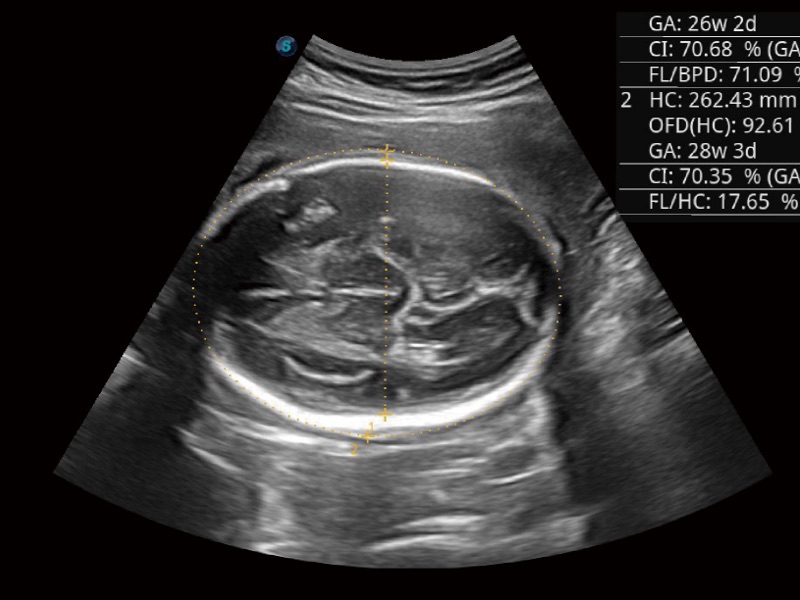

• 妇产科应用

临床图